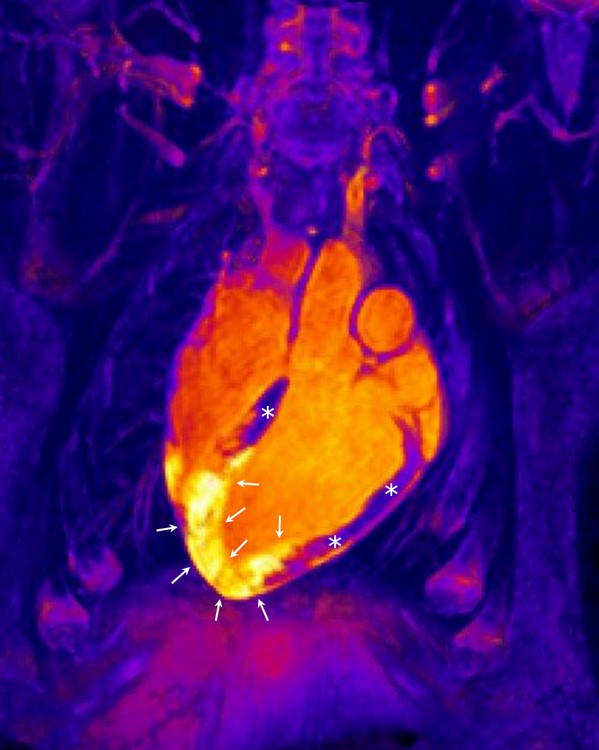

(*) NOTA DE FOTO: Imagen de resonancia magnética tridimensional en un sujeto tras un infarto agudo de miocardio. En el centro de la imagen aparece el corazón. El músculo cardiaco sano (no infartado) está marcado con asteriscos, mientras que las flechas señalan la región de corázon que ha sufrido el infarto. Con resonancia magnética se puede visualizar la extensión de area de inflamación y edema tras el infarto (zona amarilla señalada con las flechas). Haciendo resonancia magnéticas seriadas, se puede ver como esta reacción inflamatoria aparece inmediatamente tras el infarto pero luego se resuelve muy rápido para luego volver a aparecer días tras el infarto.

Durante décadas se ha asumido que, inmediatamente después de un infarto, se producía una reacción inflamatoria (caracterizada por un incremento del contenido de agua y células) en el tejido infartado y que ésta permanecía estable durante al menos una semana con una posterior desaparición progresiva. Hace dos años este mismo equipo publicó una serie de trabajos en un modelo experimental donde se cuestionaba este viejo dogma, pero lo más importante quedaba por demostrarse: la validez del nuevo paradigma en humanos. Este nuevo trabajo, que ha hecho uso de la tecnología de resonancia magnética más avanzada para demostrar que el corazón humano responde con dos reacciones edematosas muy bien diferenciadas y separadas en el tiempo, tiene implicaciones clínicas inmediatas que afectan no sólo a ensayos clínicos en marcha, sino a futuros estudios que puedan enfocarse en la modulación y posible tratamiento de estas dos fases independientes.

El descubrimiento de la reacción bimodal del corazón humano, “hace replantearse el momento en el que los ensayos clínicos deben realizar una resonancia magnética para cuantificar el daño irreversible de los pacientes y el efecto de terapias aplicadas para reducir este daño. Hasta ahora existía una visión liberal y estos estudios de imagen cardiaca se realizaban en cualquier día post-infarto. Estos nuevos trabajos nos muestran que las resonancias magnéticas con este objeto deben de realizarse entre el día 4 y 7 post-infarto, momento en el que la segunda onda inflamatoria/edematosa es prominente y ocupa toda el área que estuvo sin riego sanguíneo durante el infarto”, señala el Dr. Ibáñez, recientemente galardonado con el Premio a la Investigación Biomédica de la Fundación Banco Sabadell.